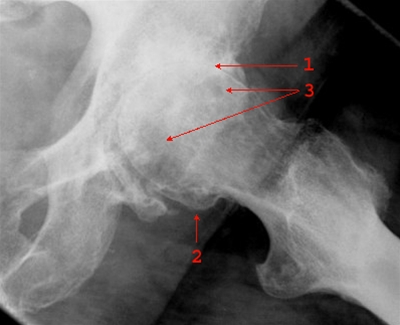

Sideoptagelse, der viser udtalt artrose i venstre hofteled med næsten udslettet ledbrusk og ledspalte (1), randudbygning af osteofytter (2) og subkondral sklerosering og cystiske opklaringer (3).